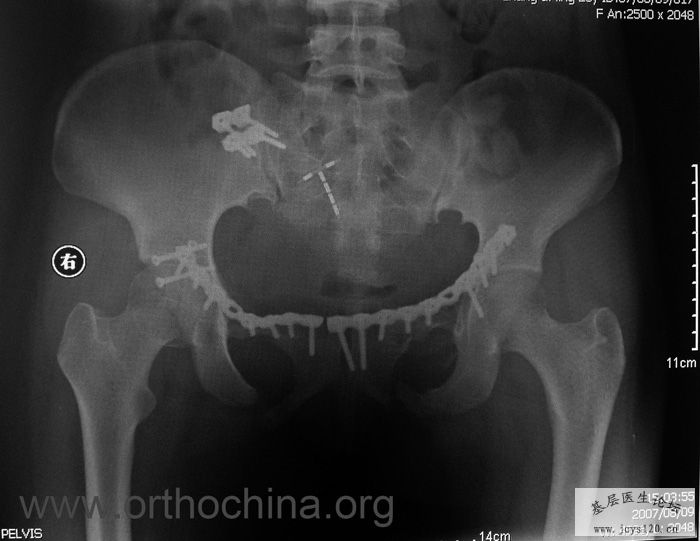

患者,女,28岁,车祸中骨盆轧伤后疼痛功能障碍1小时。查体:休克外貌,烦躁不安。头颈胸腹无异常,脊柱无异常,两下肢血供及感觉正常。骨盆挤压分离试验阳性。阴道、尿道、直肠、腹内脏器无损伤。住院后抗休克、骨牵引及对症治疗1周后,行前后联合入路手术。股骨头骨折复位后用可吸收螺钉固定,骶髂关节、髋臼前后柱、对侧耻骨上下支用骨盆重建钛板固定,术中出血1200ML,手术时间8小时。部分图片如下: